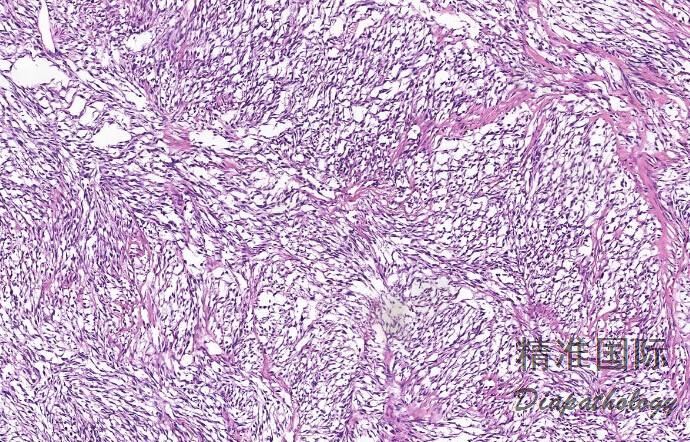

- 镜下由束状、巢状或片状的瘤细胞组成,其间为纤细的结缔组织间隔分隔;

- 瘤细胞呈多边形、卵圆形或胖梭形,胞质丰富嗜酸性或透亮,核呈圆形或卵圆形,淡染或呈空泡状,可见明显的嗜伊红色或嗜双色性核仁,有时可见多核瘤巨细胞;

- 可见核分裂像,一般<3 ~ 5 个/10HPF;

- 部分病例瘤细胞内可见黑色素颗粒,少数病例可见间质明显的黏液变性。